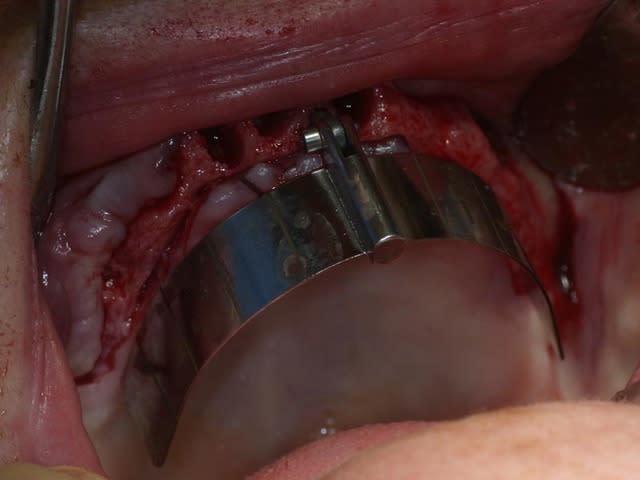

bon, toujours aussi speed je suis, mais après certaines réclamations, et malgrès ma réticence à poser un cas non "consolidé", voici en avant première mon premier all on 4, version photos ratées et non retouchées, mais... speed je suis je vous disais ;)

sto le bla bla, et pasons le diaporama... bon voyage au pays de la mise en charge immédiate totale au maxillaire de fille carole sur dame ginette, une patiente en or que j' adore, et pour qui je suis très très heureuse d' avoir pu réaliser cette chirurgie et la première étape prothétique.....